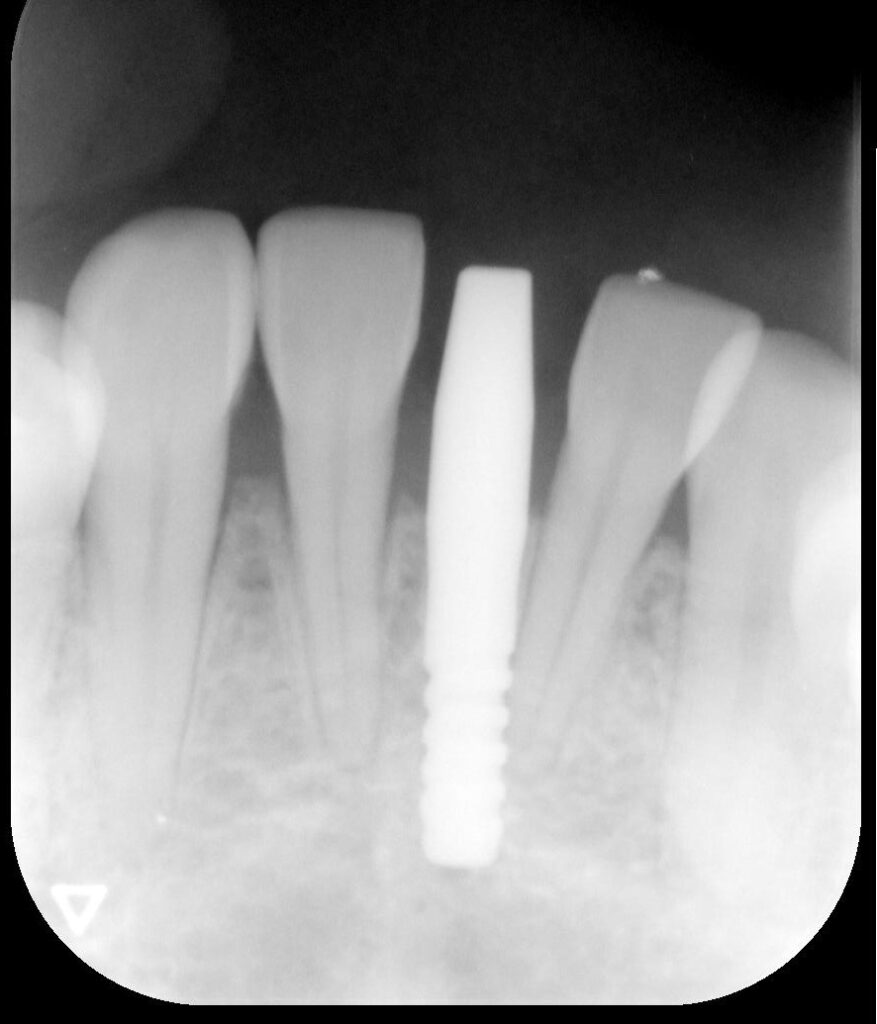

開けた穴に、専用道具を使ってネジを締めるように長さ2センチ程のインプラントを骨に埋め込んでいきます。

しっかりとインプラント埋め込まれた後は、動揺がないか、噛んだ時に当たらないかなどを確認して、最後にパノラマ写真を撮影して今回のオペは終了となりました。